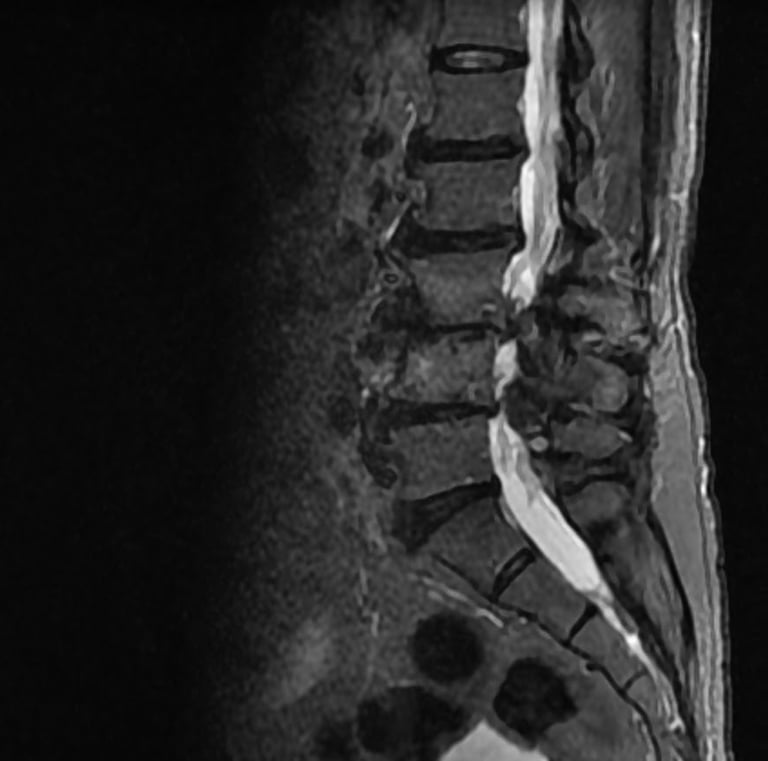

Galería

Momentos que reflejan dedicación y cuidado humano.